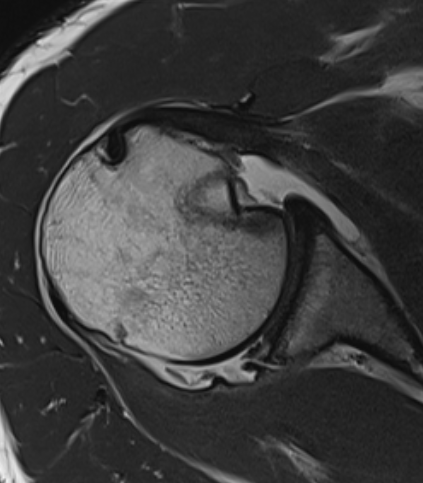

MRI

Chronic posterior shoulder dislocation with humeral head remodelling and glenoid bony deficiency